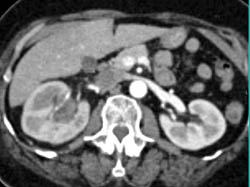

Duplicated Upper Pole Right Kidney